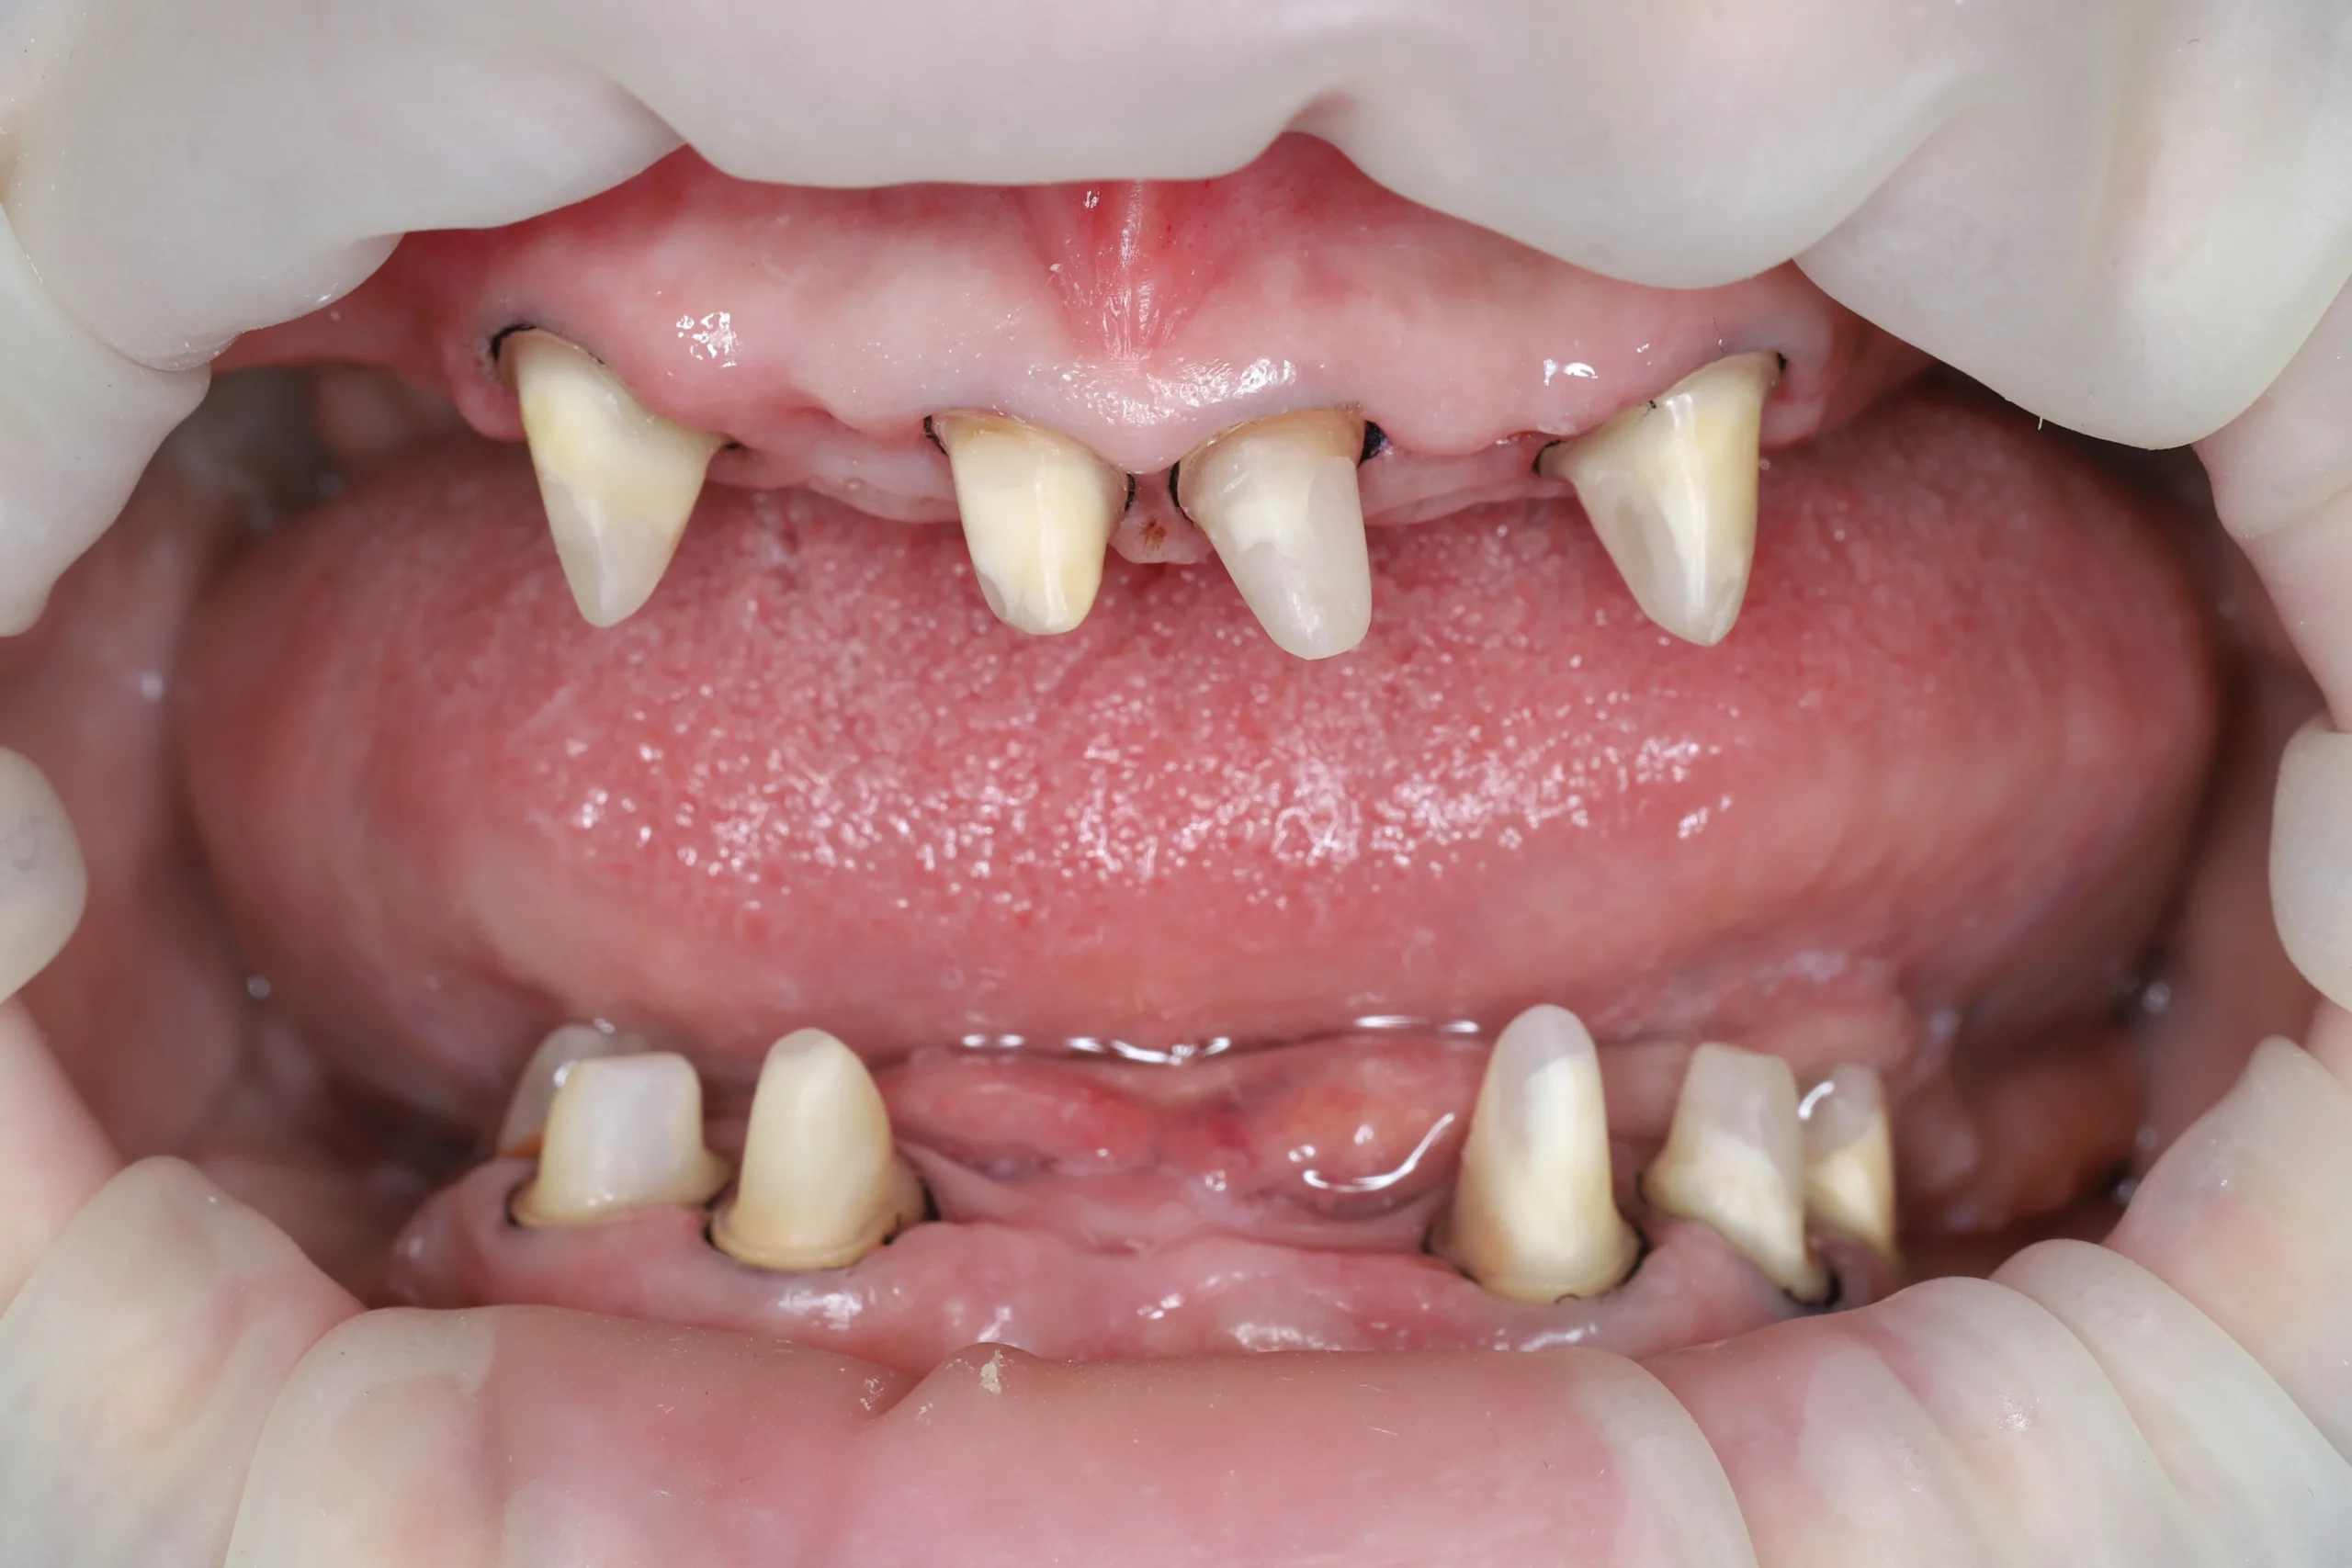

Основная жалоба пациентки — жалобы на подвижность зубов, разрушение и утрату значительного количества зубов, неприятный запах изо рта, эстетический и функциональный дискомфорт во время жевания и общения.

Диагноз: хронический генерализованный пародонтит со вторичной адентией во всех сегментах челюстей. Стадия декомпенсации, с глубокими пародонтальными карманами и потерей костной поддержки вокруг сохранившихся зубов. Гноетечение из пародонтальных карманов.

Было проведено одномоментное удаление всех зубов, не подлежащих дальнейшему лечению. Наложены швы, даны рекомендации по уходу.

После снятия швов пациентке выполнили комплексную чистку оставленных зубов.